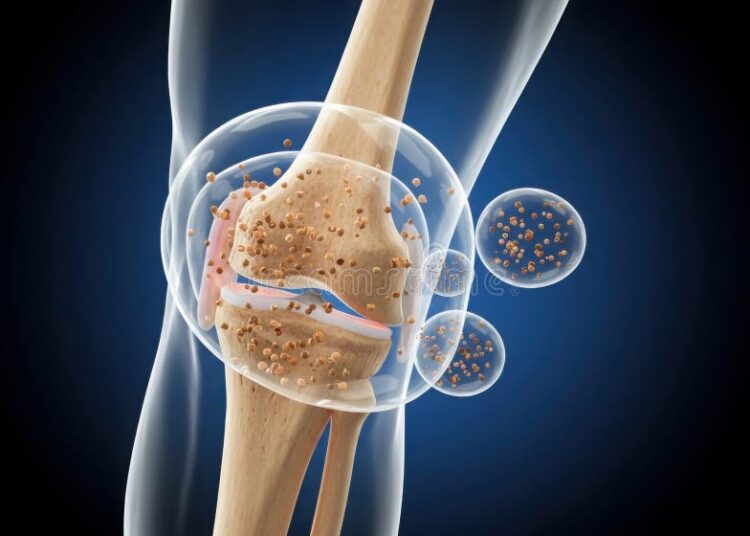

La paradoja del cartílago: Se muere si no se mueve

¿Cómo sobrevive entonces? (El Efecto Esponja) La biología ha resuelto este problema con un mecanismo hidráulico ingenioso. El cartílago funciona ...